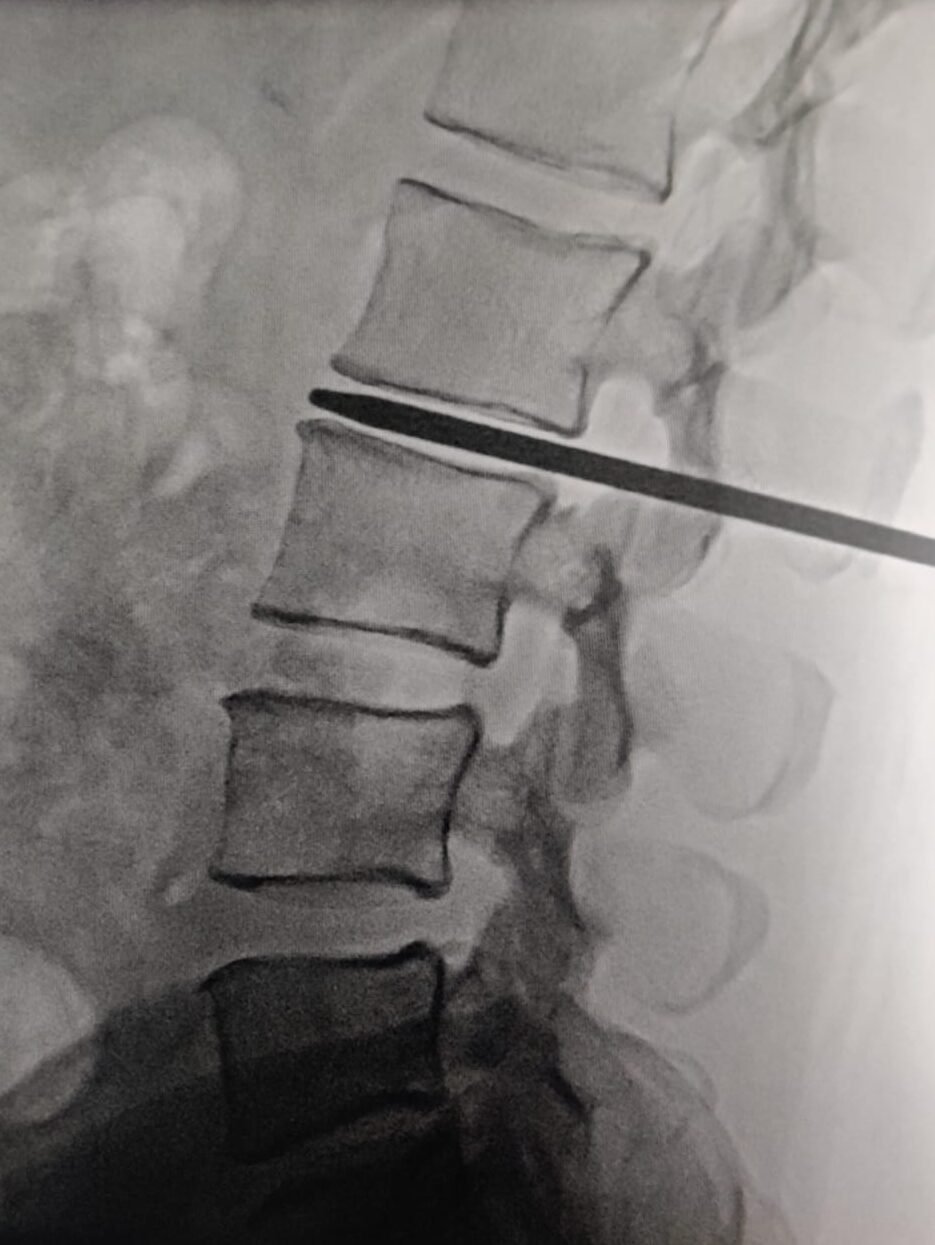

2️⃣ Interventional Pain Management

For persistent pain not responding to conservative care:

- Epidural steroid injections

- Selective nerve root blocks

- Targeted image-guided procedures

These treatments reduce inflammation and allow natural healing.